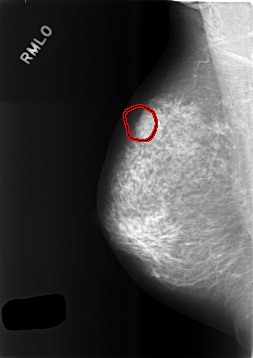

ics_version 1.0 filename C-0475-1 DATE_OF_STUDY 2 10 1995 PATIENT_AGE 66 FILM FILM_TYPE REGULAR DENSITY 2 DATE_DIGITIZED 10 2 1999 DIGITIZER LUMISYS LASER SEQUENCE LEFT_CC LINES 5616 PIXELS_PER_LINE 3944 BITS_PER_PIXEL 12 RESOLUTION 50 NON_OVERLAY LEFT_MLO LINES 5696 PIXELS_PER_LINE 4064 BITS_PER_PIXEL 12 RESOLUTION 50 NON_OVERLAY RIGHT_CC LINES 5728 PIXELS_PER_LINE 3936 BITS_PER_PIXEL 12 RESOLUTION 50 OVERLAY RIGHT_MLO LINES 5720 PIXELS_PER_LINE 4040 BITS_PER_PIXEL 12 RESOLUTION 50 OVERLAY |

FILE: C_0475_1.RIGHT_MLO.OVERLAY TOTAL_ABNORMALITIES 1 ABNORMALITY 1 LESION_TYPE MASS SHAPE LOBULATED MARGINS MICROLOBULATED ASSESSMENT 4 SUBTLETY 5 PATHOLOGY BENIGN TOTAL_OUTLINES 1 BOUNDARY |